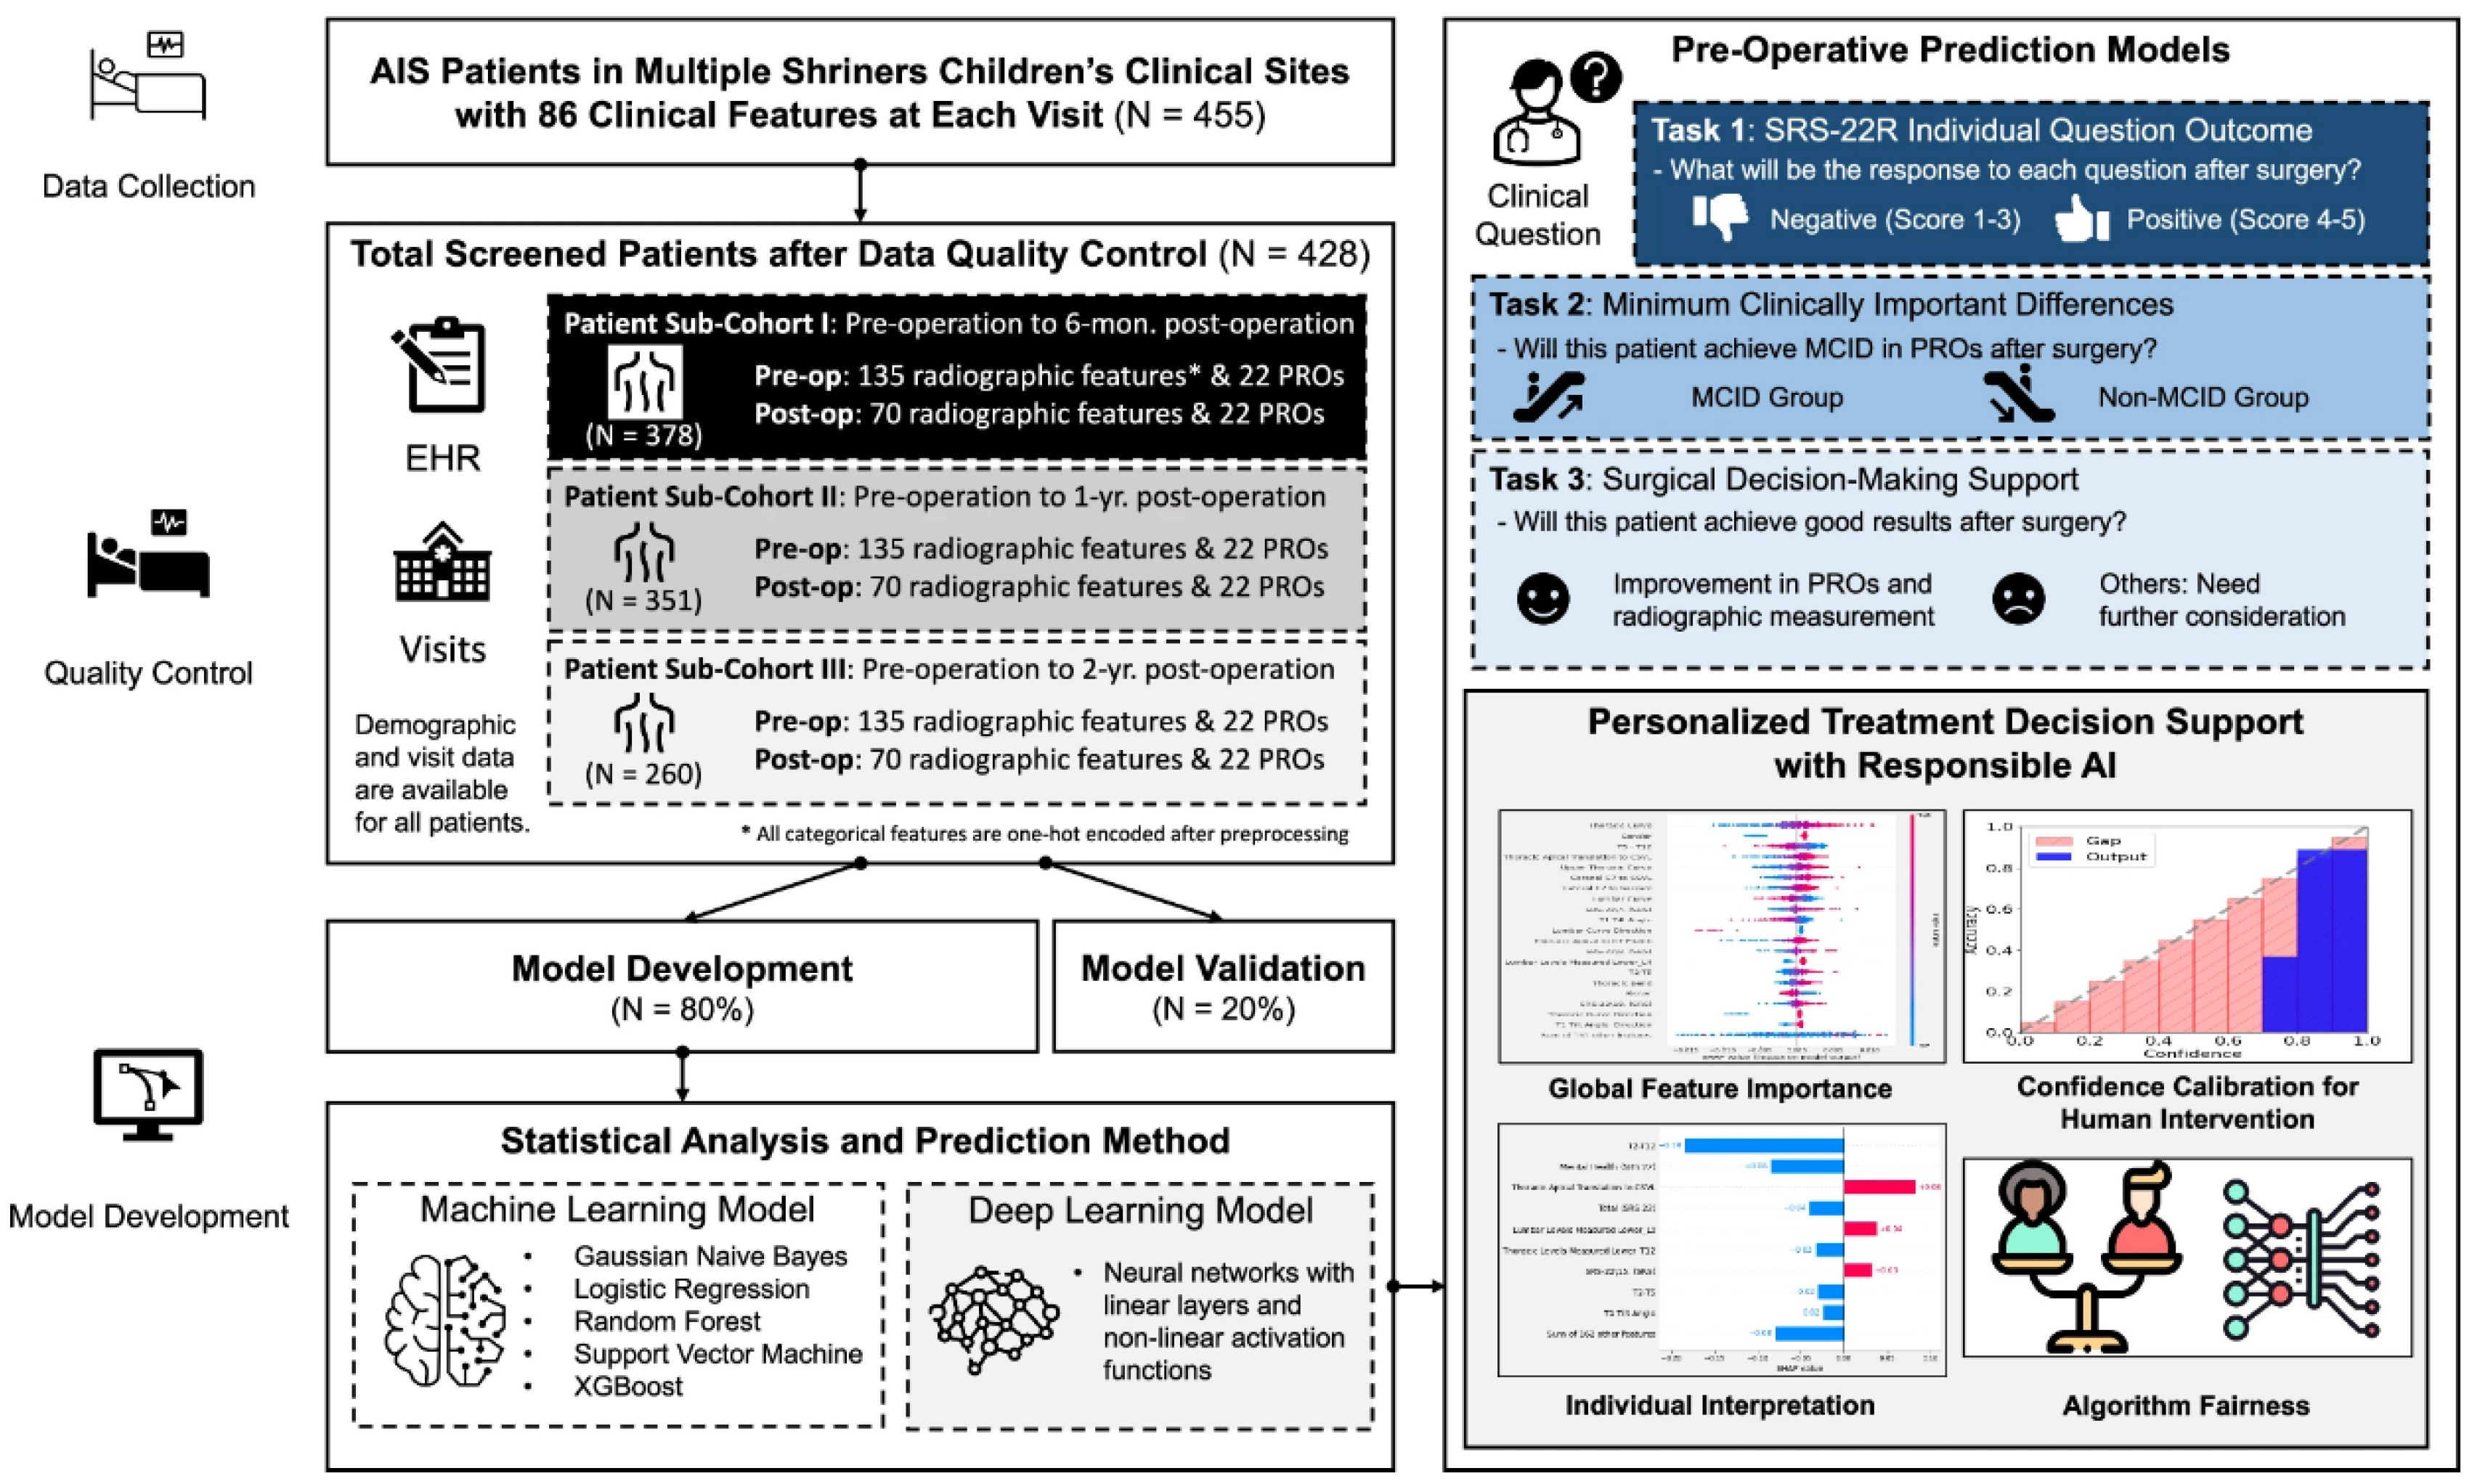

Another group of researchers has successfully developed an AI-enabled surgical planning and counseling support system to predict postoperative outcomes in AIS patients undergoing posterior spinal fusion (PSF) surgery, using a rare multi-site cohort of 455 patients from Shriners Children’s hospitals [

27]. The model predicts three key outcomes to support shared decision-making: individual responses to the refined Scoliosis Research Society-22 (SRS-22R) questionnaire, likelihood of achieving clinically meaningful improvements, and changes in both radiographic measurements and patient-reported outcomes (PROs). To the authors’ knowledge, it is the first known model to predict SRS-22R responses post-PSF, leveraging follow-up data spanning 6 months to 2 years. The framework integrates explainable AI techniques to identify important predictive features, calibrates model confidence for appropriate human oversight, and addresses gender bias (

Figure 8).